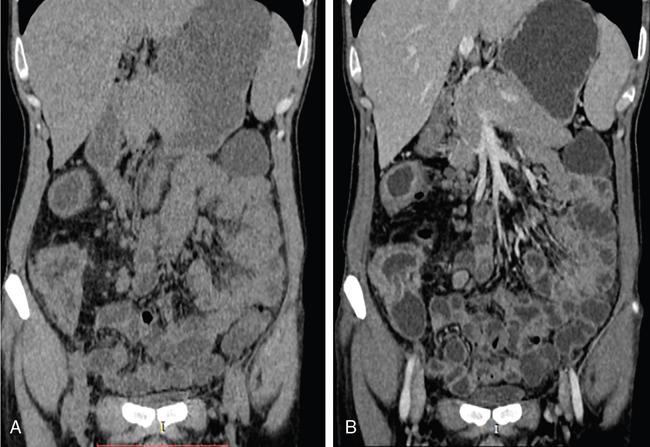

SMALL BOWEL IMAGING Poonam Narang, Himanshu Gupta The small bowel is a long tubular hollow abdominal viscus thrown into intricate folds and loops and packed into the abdominal cavity. It is approximately 5–7 m in length and extends from the gastric pylorus up to the ileo-caecal valve. It is anatomically divided into three parts: duodenum (meaning ‘in twelves’ as its length is roughly equal to the width of 12 fingers), jejunum (meaning ‘fasting’ as it was usually found empty after death) and ileum. The duodenum measures 20–25 cm in length and extends from gastric pylorus to the ligament of Trietz. It is a fixed ‘C’-shaped structure that cradles pancreatic head in its concavity. First part of the duodenum is a triangular conical structure with its base communicating with gastric antrum. Its apex points to the right and cranially, in close apposition with the gall bladder and the under surface of the liver. Second part of duodenum is almost vertical, lying in the right paravertebral gutter. The common bile duct courses obliquely posterior to it and drains at a papilla at its medial wall (the Ampula of Vater), after joining with the main pancreatic duct. Third part is horizontal, crossing the midline between the superior mesenteric artery (SMA) and aorta from right to left, caudal to pancreatic neck. Fourth part is again almost vertical, ascending left of the spine almost to the level of duodenal bulb and transitions to jejunum at duodenojejunal (DJ) flexure. Duodenum is mostly a retroperitoneal structure while the rest of the small bowel acquires a mesentery at the DJ flexure. The jejunum and ileum are intraperitoneal structures, suspended in the abdominal cavity from the posterior abdominal wall by the free end of their ‘fan-shaped’ mesentery and are thus relatively mobile. Though considered a part of small bowel, duodenum differs from the rest of the small bowel in structure as well as function. Plethora of the diseases that affect duodenum are distinct. Peptic ulcer disease affecting the first part does not affect the rest of the small bowel. Most other diseases affecting the duodenum arise from the surrounding structures like pancreas, gall bladder, bile duct, liver and the hepatic flexure of colon. Hence, on imaging, duodenal abnormalities should prompt a search for pathologies of the surrounding organs. While duodenum is structurally a distinct segment, the structural transition from jejunum to ileum is seamless, with no external demarcating point. Histologically, and also on imaging, all three segments have clear identities. Their mucosal lining, folds and presence of submucosal lymphoid follicles are allocated in accordance with their specific functions. Jejunal loops occupy left hemiabdomen and ileal loops, with ileo-caecal junction, lie in the right lower abdomen. Jejunum is about two-fifths of the length of the small bowel, and the ilium forms the rest of the three-fifths of the entire 5–7 m. ‘Terminal ileum’ is a term arbitrarily but commonly used in clinical practice to denote the portion of ileum just proximal to ileo-caecal junction harbouring abundant lymphoid tissue in its walls and playing host to a number of pathologies. At ileo-caecal junction, the ileum joins the caecum obliquely. A valve-like mucosal fold regulates the flow of digested food into the colon and prevents its reflux back. Its efficiency in preventing reflux is quite inconsistent in a large percentage of subjects. The arterial supply of the duodenum is by the branches of hepatic artery (branch of Celiac Axis artery), till the proximal half of second segment (marked by the Ampula of Vater); and by branches of the superior mesenteric artery beyond that point. Duodenal branches of respective superior and inferior pancreatico-duodenal arteries make an arcade along the medial margin of duodenum in the pancreatico-duodenal groove. The rest of the small bowel is supplied by the superior mesenteric artery and its branches while venous drainage is via superior mesenteric vein and its tributaries. These vessels traverse the mesentery, between the twofolds of the peritoneum from the posterior abdominal wall to reach the small bowel forming multiple arcades of vessels within the mesentery. Straight arteries, called the Vasa Recta, arise from the terminal arcade and enter the bowel wall, along its mesenteric border. Disease processes involving the specific artery affects the respective bowel segment that it supplies. Ischaemia, infarction and haemorrhage can be attributed to and localized correctly based on the relevant vascular anatomy. Inflammatory diseases cause engorgement of Vasa recta; and at times, identifying them as a lead point, one is able to localize the involved bowel segment correctly. Vascular ischaemia affects the antimesenteric part of the bowel earlier in the course of the disease. Therapeutic procedures too can be appropriately planned based on the vascular territory of the affected bowel segment. The mesentery forms a fan-shaped suspensory support, tethering the small bowel to the posterior abdominal wall, along a line running obliquely from ligament of Trietz (in LUQ) to ileo-caecal junction close to superior part of right sacro-iliac joint (in RLQ). This ‘root of mesentery’ averages about 15–20 cm in length. It is closely wrapped around small bowel loops and merges with the serosa. All lymphatic and vascular channels supplying to and draining from the small bowel traverse within the mesentery. Thus, pathology originating in one often affects the other by contiguity, haemodynamic alteration or haemo-lymphatic spread. The normal mesentery sandwiches a layer of fat between its two leaves. On imaging, it provides a good background against which identification of pathologies of fluid density (oedema) or soft tissue density (phlegmon, lymph nodes, masses) can be made. Mesenteric oedema often becomes the smoke leading up to the fire, for example: focal oedema adjacent to the site of an otherwise invisible bowel wall perforation. On ultrasound, such tell-tale inflammation is seen as an increase in the echogenicity of mesenteric fat adjacent to the site of bowel pathology. On CT, the hypodense fat becomes hyperdense whenever any pathological change occurs. Delineation of mesenteric vessels is also facilitated due to surrounding hypodense fat. Engorged Vasa recta are easy to identify on imaging as they stand out against the surrounding fat in the mesentery. Similar imaging findings can be extrapolated to MR as well. Similar to the rest of the gastrointestinal tract, the small bowel wall comprises four layers (strata) – from within outwards being mucosa, submucosa, muscularis propria and serosa. Mucosal folds (Valvulae Conniventes) and further finger-like projections of mucosa (Villi) help dramatically increase the surface area for absorption. Only valvulae conniventes are seen radiologically as concentric rings measuring 2–3 mm. The bowel wall measures 1–2 mm when distended and 2–3 mm when collapsed symmetrically in its entire circumference. Increased bowel wall thickness (in the background of adequate luminal distension) is a commonly used marker of pathology. Understanding how different pathologies target specific sites within the micro-structure of bowel wall, along with length of bowel involvement, could be helpful in drawing conclusion regarding the etiopathogenesis. For example, short segmental disruption of the entire thickness of bowel wall favours a unifocal, infiltrative pathology-like malignancy. Long segment submucosal oedema with preserved mucosal integrity/enhancement may be a haemodynamic phenomenon as in portal enteropathy or reactive as in infective enteritis. Depth and invasiveness of a disease process can be monitored for activity/progression, especially on imaging modalities like ultrasonography and MRI. The innermost anatomic layer of small bowel wall, its mucosa forms the absorptive surface which transports nutrients from the lumen into blood/lymph. Pathologies affecting the mucosa cause reduction (shortening) in the available area of absorption – the so-called short bowel syndrome. A variety of metabolic derangements can accompany the nutritional deficiencies caused thereby. Many other inflammatory and infiltrative diseases like lymphomas cause various alterations in the appearances of mucosal folds. Reduction, blunting, flattening, thickening, clubbing, nodularity, polypoid formation, etc. are various imaging appearances of the disease processes affecting the mucosal surface (Figs. 8.3.1.1–8.3.1.3). These abnormalities can be local, segmental, regional or generalized; involving the entire circumference, mesenteric or antimesenteric regions. The radiologist’s role thus lies in identifying the presence, location and extent of mucosal abnormality in addition to suggesting a possible aetiology based on the specific clinical settings. Small bowel has no sensory or motor nerve supply and is regulated by autonomic nervous system for its motility, secretions and absorption. Branches from vagus nerves and from dorsal sympathetic ganglion also traverse the mesentery to innervate the bowel wall at the mesenteric border. During the third week of intrauterine life, the process of ‘gastrulation’ results in formation of three basic layers, namely ectoderm, mesoderm and endoderm, which eventually evolve and differentiate into tissues and organs of all systems. Bowel, along with hepatobiliary and pancreatic system, develops from the ‘primitive gut tube’ that is formed when the endoderm folds upon itself. It then differentiates into three sections: foregut, midgut and hindgut. By 4–6 weeks, the rapidly growing intraabdominal organs outgrow the coelomic cavity. The midgut undergoes physiological umbilical herniation and rotation and then herniates back into the abdomen by the 10th week. Subsequently, the developed midgut organs undergo peritoneal incorporation and fixation to occupy their respective intraabdominal positions. This process takes place in three stages, and interruption at each stage results in specific anomalies of malrotation and peritoneal fixation. During the first stage, from week 6 to week 10, the midgut herniates ventrally into the umbilical cord in a vertical loop configuration. This loop has the superior mesenteric artery in the centre dividing the midgut into a prearterial (jejuno-ileal) segment superiorly and a postarterial (caeco-colic) segment inferiorly. This loop rotates 90 degree counter-clockwise, with superior mesenteric artery as its axis. The prearterial segment comes to lie to the right and the postarterial segment to the left in a horizontal plane. The second stage, from week 10 to week 12, results in a further 90-degree counter-clockwise rotation, and the small bowel loops now are positioned under the postarterial segment. By the end of the 10th week, the abdominal cavity grows large enough to accommodate the entire length of the foetal bowel. As the bowel loops now return to the abdominal cavity, the small bowel returns first followed by the large bowel. Subsequently, the small bowel loops make their final 90-degree counter-clockwise rotation, bringing the D-J junction to the left of the spine, while the colon makes a 180-degree rotation in the same direction to place the caecum in the right lower quadrant of the abdomen. Thus, by the end of stage II, the midgut derivatives have undergone a total 270-degree rotation (including the initial 90-degree rotation) with DJ junction to the left of midline, caecum in the right lower quadrant and transverse colon crossing in front of the duodeno-jejunal junction. Vitello-intestinal duct (VID) gets obliterated by the ninth week. The third stage (from 12 weeks until term) involves fixation of the mesenteries to the posterior abdomen. The completed normal rotation of the bowel produces a long mesenteric attachment for small bowel, extending from ligament of Treitz at the D-J junction in left upper quadrant to the ileo-caecal valve in right inferior quadrant known as the ‘root of mesentery’. The dorsal mesentery of some portions of the gut, like pancreas, duodenum, ascending and descending colon, becomes incorporated into the posterior abdominal wall, making these segments secondarily retroperitoneal (Figs. 8.3.1.4–8.3.1.6). Understanding of chronological embryology helps one to interpret respective imaging features of developmental anomalies and also to look for their associations. During imaging of a suspected case of malrotation, position of DJ flexure, ileo-caecal junction, relative location of jejunal and ileal loops and relation of superior mesenteric artery to the accompanying vein help in reaching the correct conclusion. It should be kept in mind that certain diseases (notably the celiac disease and other malabsorption syndromes) may invert the imaging morphology of jejunum and ileum leading to erroneous diagnosis. Evaluation of orientation of superior mesenteric vessels and the duodeno-jejunal junction would help resolve any ambiguity in such cases (Figs. 8.3.1.7 and 8.3.1.8). Developmental malrotation is often a precursor to small bowel volvulus, or obstruction by extrinsic bands in neonates and infants. In adults, on the other hand, often the malrotations are by themselves, asymptomatic. They get identified only incidentally, or while looking for symptoms due to their associations. Preduodenal peritoneal bands, commonly called as the Ladd’s bands, causing external compressions resulting in bowel obstruction are less common. Often, peritoneal fenestrations and deep fossae, associated with developmental midgut malrotations, present with internal bowel herniations like various para-duodenal and mesenteric herniations. One must be aware of their associations, so as to make the correct interpretation. Internal hernias may be a cause of intermittent postprandial abdominal pain, when reducible; or may result in acute bowel obstruction. They are identified by abnormal location and clumping together of the relatively mobile small bowel loops. High degree of suspicion and knowledge about their locations, helps one to diagnose them with more confidence. Occasionally, constrictions at the neck of hernia can also be identified. Fluoroscopic examination, with palpation to separate the opacified loops, provides the most confident method of their identification. The origin of clinical abdominal radiography dates back to 1896–97, soon after the discovery of X-rays by Wilhelm Roentgen in 1895, when E. Lindemann used X-rays to demonstrate gastroptosis and Walter B. Cannon used them to describe basic physiology of swallowing and peristalsis. The biggest shortcoming with plain abdominal radiographs was lack of inherent contrast with only occasional visualization of air-filled stomach. H. Rieder introduced the concept of contrast abdominal radiographs by giving patients large amounts of radio-opaque bismuth orally, followed by rapid serial abdominal radiographs for better luminal visualization. Later, C. Bachem and H. Gunther introduced barium as inert and nontoxic contrast agent for gastrointestinal imaging. Since their inception, conventional imaging techniques, like plain abdominal radiograph, fluoroscopy and single contrast barium studies, formed the cornerstone of abdominal imaging despite their limitations. In the mid-20th century, with the availability of better barium preparations and advancements in fluoroscopy and radiographic equipment, such as tilt tables, better films and image intensifiers, double contrast barium studies became the problem-solving technique due to its unparalleled ability to image gastrointestinal mucosa meticulously. This enabled the mucosal morphology to be imaged in detail, thus aiding detection of even minute mucosal lesions such as small ulcerations and early carcinomas. With the invention of flexible endoscopes in the late 20th century, UGI endoscopy and colonoscopy replaced abdominal radiography as the frontline investigation for evaluation of the upper GI tract (oesophagus, stomach and duodenum) and colon, respectively, with added advantage of direct lesion visualization and obtaining biopsy. Owing to its length and complex folded anatomy, small bowel is still inaccessible via flexible endoscopes except for a few centimetres of proximal jejunum and terminal ileum. One of the major drawbacks of barium studies and endoscopy was that they provided solely luminal details with lack of information about mural and extramural structures. This ushered the era of modern imaging modalities with cross-sectional capabilities like US, CT and MR. With ongoing advancements in equipment, imaging techniques and contrast media, these modalities are at the forefront of the modern GI imaging, offering better and detailed answers to clinical questions being asked. With recent introduction of capsule endoscopy, gastroenterologists are trying to find a place in noninvasive evaluation of small bowel, but it still has a long way to go. Till then, small bowel evaluation continues to be the radiologist’s domain. Imaging of the small bowel has traditionally played an important role in clinching a diagnosis due to its relative inaccessibility for direct endoscopy. Even with the advent of capsule endoscopy for mucosal evaluation, imaging retains its position in the diagnostic algorithm for its ability to evaluate full thickness of bowel wall and extraluminal structures, in addition to providing information regarding its lumen. Imaging also provides information about the bowel motility, directly or indirectly. Ultrasound and fluoroscopy provide real time visualization of peristalsis. CT scan with oral contrast may be used to monitor transit in certain specific situations, for example in postoperative settings, to differentiate paralytic ileus from mechanical obstruction. Small bowel anatomy as well as pathology can be assessed and compared on various imaging modalities under the following headings: Plain abdominal radiographs have a limited role in modern small bowel imaging. It gives relatively little diagnostic yield, and most modern departments have easy availability of US, CT and MRI. In setting of acute abdomen, plain abdominal radiographs have greatest value in evaluation of pneumoperitoneum; gas patterns and air-fluid levels in bowel obstruction; enteroliths; radio-opaque foreign bodies; and to a limited extent, in the evaluation of bowel wall pattern in cases of bowel ischaemia/colitis. A good supine abdominal radiograph helps to evaluate gas pattern and bowel calibre. The kilo-voltage should be low, preferably 60–75 kV, to maximize contrast. Exposure time must be short to minimize motion blur. It should cover the entire abdomen from domes of diaphragm to the inferior border of pubic symphysis, including obturator foramina (hernial orifices). The X-ray beam should be centred at the level of iliac crests with proper collimation. An adequate erect abdominal radiograph should suffice to demonstrate air-fluid levels and free peritoneal gas in cases of pneumoperitoneum, with erect chest x-ray (CXR), and left lateral decubitus radiographs being reserved for suspicious cases of small pneumoperitoneum. It is advisable to keep the patient in an erect position for at least 10–12 minutes before taking erect CXR or erect abdominal radiograph and in left lateral decubitus position before taking left lateral decubitus radiograph to allow free air time to rise to the highest point. Erect chest radiographs are more sensitive and reliable due to better visualization of free air forming sharp margins with diaphragm and liver surface, respectively. Normally, small amount of intraluminal gas is seen in nondilated small bowel loops. Three or more air-fluid levels measuring more than 2.5 cm in width are abnormal for small bowel and indicate stasis. Increased aerophagia or laboured breathing may sometimes give a peculiar appearance on radiographs called as ‘meteorism’. The small bowel loops appear distended with air, mimicking stasis. However, due to minimal fluid content, no abnormal air-fluid level is seen on accompanying erect radiographs. However, it is now recognized that the number, distribution and length of air-fluid levels on erect abdominal radiograph cannot reliably differentiate between obstruction and ileus and can be often misleading (Figs. 8.3.1.9 and 8.3.1.10). It must be mentioned here that plain X-ray abdomen has retained its popularity in healthcare settings that lack modern infrastructure like CT scanner in the Emergency Department. A rapid, low-dose CT scan of the abdomen gives much more information with higher degree of confidence as compared with that provided by a set of plain radiographs. Barring the cost and availability, low-dose noncontrast CT scan should replace plain radiography in patients presenting with acute abdomen. The earliest enteric contrast media used in GI tract imaging was iodized oil (Lipiodol). However, due to its oily nature, it did not coat the mucosa. At present, medical grade bismuth sulphate is the contrast media of choice for GI imaging. The reasons for using barium sulphate are: Barium studies have been the most reliable conventional techniques in small bowel imaging since their inception and still remain unmatched in detecting luminal dilatation or narrowing, subtle mucosal alterations and motility disorders. One of the major inherent limitation of conventional barium studies is the lack of information regarding extraluminal/extraintestinal structures. Duodenum is usually studied along with the stomach, using high-density barium suspension. Single or double contrast technique can be used, depending on the information sought. Only in cases where duodenal obstruction, diverticulum, fistula or leak needs to be demonstrated, a single contrast study using barium or gastrografin (in suspected cases of peritoneal leak) is performed. Double contrast studies require special manoeuvres to distend the lumen with air after coating the mucosa with a layer of barium. The patient is positioned in right or left lateral- oblique position, and images are taken under flouroscopic view to demonstrate barium coated, distended and then a collapsed duodenal bulb; and C loop till the DJ flexure. Duodenal ulcers usually deform and contract the symmetrical and conical duodenal bulb. Strictures or focal narrowing of the second part of duodenum can be due to congenital or inflammatory diseases. Widening of C loop indirectly reflects enlargement of pancreatic head. A small or large diverticulum along its medial wall adjacent to Ampula of Vater is seen in many subjects and is mostly incidental. Mucosal folds of the duodenum, seen in relief, can demonstrate focal or regional inflammatory/infiltrative processes. For fluoroscopic barium studies of the jejunum and ileum, a large amount (500–600 mL) of thinner suspension of barium sulphate is given orally; and flouroscopic images with local compression are taken at intervals of 20–30 minutes, till most of the barium reaches and distends the caecum; and ileo-caecal junction is demonstrated. To improve visualization of the ICJ, caecum can be insufflated with per-rectal air. This technique is called as per-oral pneumocolon and is mostly used in countries where diseases like tuberculosis that involve the ICJ are common. Enteroclysis too can be performed to better visualize the small bowel without opacifying the stomach and duodenum. The technique also achieves a continuous, unbroken column of barium without segmentation caused by intermittent gastric emptying. A nasogastric tube of 10F is introduced over a guidewire, to position its tip just beyond the ligament of Trietz. About 1200–1500 mL of barium is pumped manually, or by an automated pump under fluoroscopic vision to opacify the entire small bowel. It may be followed by 0.5% methyl cellulose if a double contrast study is desired. The rate of instillation is roughly 80 mL/minute but is titrated under vision so as to obtain adequate distension without causing the column to break or inducing bowel atony. Multiple supine and oblique views are obtained with compression to separate out the overlapping bowel loops. The procedure is long and entails a large amount of radiation exposure, while providing limited information about the lumen, extrinsic impressions and displacements only. At present, its best use is in demonstrating postoperative small bowel obstruction and in resolving some cases where cross-sectional imaging is ambiguous in demonstrating partial obstructive lesions. The above description is now more for its historical value, though the technique is still practised in less-privileged departments across the world. Endoscopic studies have largely replaced barium studies of the duodenum; while cross-sectional imaging has taken over the prime status in imaging of the jejunum and ileum. With conventional fluoroscopic studies and CT enterography dominating the field of small bowel imaging, ultrasonography (US) has been an underrated diagnostic imaging tool in evaluating bowel pathologies up till now, with its role limited to diagnosing appendicitis, intussusception and hypertrophic pyloric stenosis. Operator-dependent nature of the modality, technical challenges of imaging a mobile structure and gaseous contents are the major reasons for its relative unpopularity. These factors make bowel US technically challenging and may lead to misinterpretation by less-experienced radiologists. Nevertheless, with constant improvements in US machines, development of technical experience and integration of clinical details for targeted assessment, US can emerge as an indispensable diagnostic tool in evaluating patients with known or suspected small bowel pathology. Conventional transabdominal US, with a 2–6 MHz curvilinear probe, should be performed initially on a fasting patient, with special attention to the region of pain or probe tenderness, to look for any extraintestinal cause that can explain the patient’s symptoms. It can also detect any intraluminal pathologies, thickened bowel loop along with secondary findings such as perienteric inflammation, lymphadenopathy, ascites, collections, masses and hepatic metastatic lesions in cases of suspected bowel malignancies. This is followed by high-frequency (5–15 MHz) assessment of nondistended bowel using linear probes in either bowel or neonatal abdomen presets. Some authors recommend using 4–10 MHz curvilinear array initially, followed by problem solving 6–12 MHz for good balance between penetration and resolution. Scanning parameters are so optimized that all layers of bowel wall are visualized. Practically it is almost impossible to scan/evaluate the entire length of small bowel by US, thus a quadrant-wise approach is more practical, wherein the abdomen is divided into four equal quadrants by two imaginary perpendicular lines passing through umbilicus. Bowel loops in each quadrant are thoroughly evaluated for any potential abnormality followed by evaluation of the ICJ, terminal ileum and as much part of distal ileum as possible. Use a graded compression technique with gentle sweeping movement of the probe to separate bowel loops and displace intraluminal air. Using optimal sensitivity and doppler settings, colour or power doppler imaging may be used to assess the mural, mesenteric or intralesional vascularity. The bowel under probe should be assessed for motility, mural thickness and gut signature. When viewed at high frequency, normal bowel wall consists of five alternating concentric rings of low and high echogenicity usually called the ‘gut signature’ – innermost lumen-mucosa interface (hyperechoic), thin hypoechoic muscularis mucosa, echogenic submucosa, followed by hypoechoic muscularis propria and outermost echogenic serosa (Fig. 8.3.1.11). US is the only imaging modality that can demonstrate these histological layers of bowel wall distinctly. In various pathological conditions, this gut signature may be preserved, exaggerated, diminished, disrupted or completely lost (Figs. 8.3.1.12 and 8.3.1.13). Disruption of the normal gut signature usually points towards a malignant or infiltrative pathology. Diseased bowel wall must be evaluated for mural and adjacent mesenteric vascularity. Usually in normal bowel wall, the doppler signals are negligible, but with introduction of low-flow imaging software, the operator must be habituated with the appearance of normal bowel vascularity on their US machines. Active inflammation and hypervascular lesions show substantially increased vascularity in the affected bowel segments. On the other hand, thickened bowel loops without doppler signals in wall and adjacent mesentery may indicate ischaemia. Colour doppler imaging may allow differentiation of active mural thickening (increased blood flow) from chronic mural thickening/fibrosis (decreased blood flow). Bowel pathology may extend and involve the perienteric mesentery, adjacent bowel loops or solid organs. One must be vigilant enough to look for mesenteric fat oedema, collection, interbowel free fluid and lymphadenopathy when inflamed bowel segment is visualized. Hydrosonography and sonoenteroclysis are useful techniques in evaluating small bowel on US. Introduction of large volumes of echo-poor liquid oral contrast (water, mannitol, polyethylene glycol, etc.) via either oral route (hydrosonography) or fluoroscopically placed naso-jejunal tube (sonoenteroclysis) results in adequate luminal distension of small bowel loops and displaces the intraluminal gas aiding better bowel visualization. Diagnostic accuracy of sonoenteroclysis is comparable to barium enteroclysis for detecting small bowel lesions. In the past few years, there has been a constant rise in the use of intravenous microbubble US contrast in organs other than the liver. EFSUMB guidelines recommend 2.5–5.0 mL of Sonovue (Bracco Imaging) for contrast-enhanced US of bowel. High-frequency (>7.5 MHz) linear array probes are used for demonstrating the differential enhancement of bowel wall layers. Following intravenous injection of US contrast material, peak arterial enhancement occurs after 30–40 seconds, followed by venous phase lasting from 40 to 120 seconds. High-end US machines can produce dynamic enhancement curves for quantitative analysis by placing region of interest over bowel wall or mass lesions. Real-time imaging capability of US allows for evaluating the bowel motility. Rhythmic, phasic contractions with slow antegrade propulsions are usually seen in the small bowel. Large migratory contractions may occur spontaneously and are usually seen after fasting. Various bowel pathologies tend to alter the rate of peristalsis. Hypoperistalsis is an indicator of unhealthy bowel and can be seen in inflammation, obstruction, ischaemia or infiltrative pathologies. High-grade obstruction usually shows fluid distended bowel loops with nonpropulsive ‘to and fro’ movement of the intraluminal contents. During evaluation of acute abdomen in paediatric patients, some small bowel pathologies get so convincingly diagnosed that this modality deserves a place in their imaging algorithm. Target sign, telescoping bowel sign or doughnut sign of intussusception can guide one to directly treat or further image to look for a lesion at lead point. Colour doppler interrogation can suggest the level of ischaemia in these loops. Similarly, bowel strangulation and ischaemia can be readily identified in a herniated bowel loop. Follow-up of Crohn’s disease for activity is routinely done by colour doppler imaging in departments where sinologists are trained for the job. SMA and celiac axis arteries can be individually interrogated in cases suspected of bowel ischaemia. This is especially useful in cases that are already diagnosed on CTA/MRA and need to be followed up noninvasively. In GI bleeding, USG can diagnose presence of portal hypertension and varices to clinch the diagnosis. A mention of the relative orientation of SMA and superior mesenteric vein (SMV) has already been made in diagnosis in cases of midgut malrotation where the association is found in about 60% of cases. Whirling and twisting of the two is seen in the case of midgut volvulus. In tropical countries, finding ascaris worms within small bowel loops on US is not uncommon. In correct clinical context, this finding can help reach a conclusive diagnosis. Endoscopic US (EUS) has rendered the GI tract and surrounding structures acquiescent to US evaluation combining the range of endoscopy with the diagnostic abilities of US. It couples a 5–12 MHz US probe with an endoscope. There are two types of echo-endoscopes: radial and linear. Radial echo-endoscopes are used in high-resolution diagnostic imaging, as they provide a 360-degree view that most operators are familiar with. Linear echo-endoscopes have limited field of view but are equipped with therapeutic-working channel facilitating image-guided tissue sampling and intervention. The proximity and high resolution of EUS allow a detailed image-based analysis of lesions in and around the accessible GI tract. The technique is best suited for hepatobiliary and pancreatic evaluation where they are apposed to the bowel wall. In small bowel imaging, their utility is limited to the duodenum and proximal jejunum. EUS can depict about nine distinct layers of bowel wall, as against the abdominal US which has a capability of resolving up to five layers. Identification of the involved layers can aid in differentiating ulcerative colitis from Crohn’s disease in selected patients. This also helps in improved analysis of tumour penetration and hence the ‘T’ staging. Submucosal tumours can be differentiated from extraintestinal indentations, and they can further be characterized as solid, cystic or vascular lesions (Fig. 8.3.1.14). Peri-lesional infiltration and nodes can be accurately assessed. Malignant GIST (gastrointestinal stromal tumor) can be differentiated from benign ones on follow-up, by their size (>3 cm), irregular margins and heterogeneity of echotexture. Identification of peri-lesional nodes permits accurate nodal staging and is useful during follow-up. The increasing demand to shift from invasive or surgical interventions to minimally invasive alternatives has driven the development of multiple EUS-guided interventions, and EUS-guided tissue sampling is perhaps the most useful contribution of this technique. EUS-guided endoscopic resection can also be done for mucosal tumours. The technique requires training and familiarity with the orientation and is usually the domain of the endoscopists. Other limitations of EUS remain the availability of the technique and the shallow depth of field of view. Cross-sectional imaging has now become the mainstay of bowel imaging as they allow visualization of the entire bowel along with luminal, mural and extramural manifestations in a single examination. With recent advancements, like superior detectors, thinner collimation and reduced scan time, MDCT (multi-detector computed tomography) has now emerged as the first line investigation for most bowel conditions because of its wide availability, rapid execution, superb spatial and temporal resolution and high-quality multiplanar reconstructions. Modern postprocessing techniques, such as volume-rendered images, shaded surface displays, virtual enteroscopy and the introduction of artificial intelligence (computer-aided detection) have increased the sensitivity of CT and enhanced the confidence of radiologists in picking up smaller lesions with greater accuracy. However, like any other imaging technique, CT has its fair share of drawbacks. High-radiation dose that CT entails is of significant concern especially in young patients or patients with chronic bowel conditions who would require multiple serial scans during their treatment course. Other demerit is poor mucosal delineation and subtle alterations in mucosal morphology, which are best demonstrated on barium studies. Types of enteric contrast agents: (Table 8.3.1.3). Collapsed bowel loops may give false impression of bowel wall thickening, thus mimicking pathologies or may hide one. Enteric contrast agents are necessary to adequately distend, otherwise, usually collapsed bowel loops, for better evaluation. Choice of enteric contrast agent depends on the information being sought. Neutral enteric contrast agents, with their inherent low CT attenuation (0–30 HU), provide better evaluation of mucosal, submucosal pathologies and bowel wall enhancement patterns and are best for routine CT enterography/enteroclysis. Positive agents, due to their high CT attenuation, obscure GI bleeds, mucosal and mural details. They have fewer indications; that is in evaluation of site of small mechanical obstruction, bowel perforation, anastomotic leaks, sinus/fistula patency, differentiating bowel from adjacent masses, interloop collections or lymphadenopathy. Negative contrast agents like carbon dioxide are being used in virtual enteroscopy. Water as enteric contrast agent is cheap, easily available, can be consumed in large quantities and better tolerated; however, due to its rapid intestinal absorption, distension achieved by water is highly variable and sometimes inadequate. Better bowel distension is achieved by mannitol and methylcellulose as they retain water in bowel lumen. Milk as neutral contrast is preferred in paediatric patients as hyperosmolar agents like mannitol can cause dehydration. PEG can cause watery diarrhoea in some patients. Commercially available neutral agent, VoLumen (Bracco Diagnostics, Princeton, NJ) is a 0.1% w/v barium sulphate suspension in sorbitol and produces better distension than many other neutral agents. Usually 1–2 L of oral contrast produce adequate luminal distension; however, volume to be administered should be adequately tailored according to the safety profile of the specific agent, to achieve good luminal distension with minimal side effects. Smaller volumes, depending upon patient tolerance, are recommended in patients with history of bowel resection. Patients are advised to completely restrict solid food intake for about 6 hours prior to examination. To assure better compliance, they should be well-briefed about the procedure. They are encouraged to drink at least 1.3–1.5 L of neutral oral contrast over a period of 45–60 minutes immediately prior to the study. An intravenous assess is secured with 18G or 20G cannula and saline flush is given to check patency. Slow injection of 1 mL of Buscopan (hyoscine butylbromide) is given immediately before the scan to relax bowel smooth muscles and decrease peristalsis. Scan techniques include routine plain and ‘enteric phase’ imaging performed 45–50 seconds after giving ~1.5–2 mL/kg of iso or low osmolar intravenous contrast at the rate of 4 mL/s. Multiphase CT with arterial and delayed phases is indicated while evaluating occult GI bleeds or vascular malformations. Slice thickness of 0.9 mm is adequate with reconstruction interval of 0.45 mm. CT enteroclysis is a semiinvasive imaging technique that differs from CT enterography only in the mode of enteric contrast administration. CT image acquisition remains the same. It combines the advantages of enteroclysis (good luminal distension) with cross-sectional imaging in a single examination. Large volume of enteric contrast is pumped directly into the small bowel at high rates. This volume challenge to bowel ensures better and reliable luminal distension than CT enterography, thus aiding in better evaluation of mucosal lesion and mural enhancement patterns. A good CT enterography examination with adequately distended bowel loops can demonstrate luminal, mural as well as extraluminal pathologies. Better patient tolerance and noninvasive nature has made CT enterography a preferred imaging choice in modern noninvasive small bowel evaluation. A good CT examination of the bowel can help in detecting abnormal bowel loops positioning, intussusception (Fig. 8.3.1.15), intraluminal, mural (Figs. 8.3.1.16 and 8.3.1.17) and extramural pathologies. Arterial phase images are particularly useful in evaluating the small bowel arterial supply for stenosis, strictures, thrombosis and arterio-venous malformations (AVMs) (Figs. 8.3.1.18 to 8.3.1.20). Until recently, despite excellent inherent soft tissue resolution, MR imaging had limited role in GI tract evaluation. The major hurdle being longer acquisition time, resulting in image degradation from motion artefacts due to respiratory movements and bowel peristalsis. With advancements in MR hardware and development of faster breath-hold imaging sequences, scan times have reduced considerably with minimal motion artefacts and superior image quality. When combined with good luminal distention and intravenous administration of gadolinium-based contrast media, MR provides exceptional luminal, mural and extramural details along with vascular and functional information. Increasing awareness of radiation hazards associated with high-radiation dose in CT has furthered MR enterography to the forefronts of GI imaging especially when imaging paediatric, pregnant patients or patients with chronic bowel pathologies who require sequential imaging during their disease course. Advantages of MR over CT are lack of ionizing radiation, superior soft tissue contrast, dynamic information with respect to bowel motility and relatively safer intravenous MR contrast profiles. Limitations of MR include limited availability, higher cost, longer scan time, lower spatial and temporal resolution as compared to CT and known contraindications to MR such as claustrophobia, metallic implants and pacemakers. Gadolinium-based contrast agents, especially gadodiamide, are contraindicated in patients of chronic kidney disease or renal insufficiency with eGFR < 30 mL/min/1.73 m2 due to risk of fatal nephrogenic systemic fibrosis. For adequate bowel cleansing, patients are advised to take liquid-based diet for a day with four bisacodyl tablets in the evening prior to imaging. Preprocedural fasting of 4–6 hours is advised. All this minimizes food residue and debris in small bowel which may mimic luminal pathology while interpreting the scan. Bowel distension is necessary for evaluating the intraluminal and mural pathologies as collapsed small bowel segments can mimic pathological mural thickening or hide underlying pathologies. MR imaging of small bowel makes use of enteral contrast agents to provide homogenous and adequate intestinal distension and increase contrast between lumen, bowel wall and extraluminal soft tissue. Properties of a good enteral contrast agent include easy availability, low cost, least side effects and high contrast between lumen and bowel wall. Depending on the signal intensity on various sequences, MR enteric contrast agents can be divided into positive (bright on T1w images), negative (dark on T2w images) and biphasic (dark on T1w and bright on T2w images) contrast agents. Positive contrasts like gadolinium chelates, ferrous and manganese ions and food items like blueberry juice are not commonly used as enteric contrast due to high cost, unavailability and poor distinction of mural enhancement postintravenous contrast injection. Negative contrast agents include superparamagnetic iron oxides (SPIOs) and ultra-small SPIOs (USPIOs). They are used in MR pancreatico-cholangiography to suppress the high signal from bowel luminal contents. High signal intensity of pathology or inflammation in bowel wall and surrounding fat stands out against accompanying luminal low signal intensity on T2W images. However, negative contrasts are not preferred for bowel imaging as, apart from gastrointestinal side effects like nausea, vomiting and diarrhoea, the associated susceptibility artefact can mask the hypointense signal from normal bowel wall and hide low signal intensity lesions like carcinoids on T2W images. Biphasic agents are the most commonly used enteric contrast agents in MR and include osmotic agents like mannitol, polyethylene glycol, low-density barium sulphate (VoLumen) and nonosmotic agents like water, locust gum resin and methylcellulose. Osmotic agents retain water within the lumen producing better luminal distension than nonosmotic agents; however, this may lead to mild diarrhoea postexamination. On T2W images, there is marked contrast between the high signal intensity of the lumen against dark appearing normal bowel wall, thus aiding detection of transmural ulcers, sinuses and fistula. On fat-suppressed postintravenous contrast T1W images, their inherent low signal intensity provides outstanding contrast between low signal intensity lumen, intermediate signal intensity of normal bowel wall and high signal intensity of enhancing mural/extramural inflammation or neoplasm. Enteric contrast may not be required in patients with suspected high-grade obstruction because retained intestinal fluid adequately distends the loops proximal to obstruction, and additionally administering large volumes of fluid may cause patient discomfort, vomiting or even bowel perforation. Similar to CT imaging, MR imaging of the small bowel includes two techniques of small bowel distension: MR enterography (MRE) with oral administration of the enteric contrast and MR enteroclysis, wherein the enteric contrast is infused directly into the small bowel via a naso-jejunal tube inserted under fluoroscopic guidance.

Computed tomography

CT enterography

CT enteroclysis